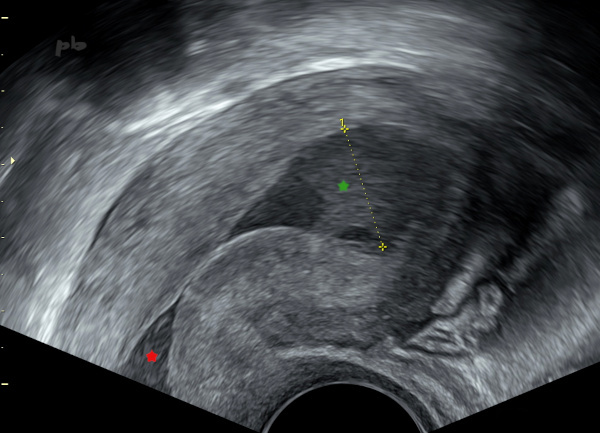

3 – Hématométrie – Sténose de l’orifice externe (OE)

Echographie endovaginale.

Rétention hématique.

La cavité utérine (croix 1) est élargie et remplie de sang hypoéchogène (★).

Il existe aussi une dilation du canal cervical (★) ou hématocolpos.